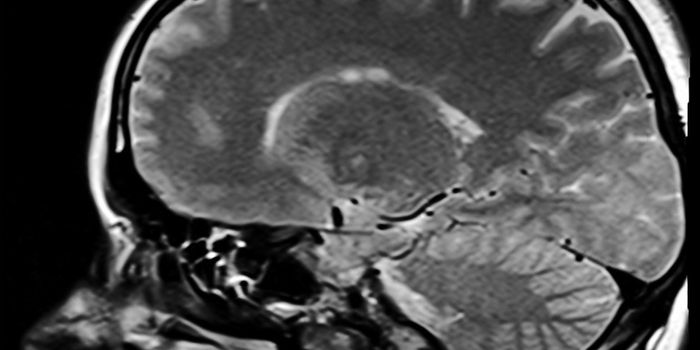

Cardiology is an ever-evolving branch of medicine concerned with disease and disorders of the heart. Cardiology trending provides articles and resources to keep you informed on risk factors, causes and prevention of heart disease, evidence-based research and advances in treatment.